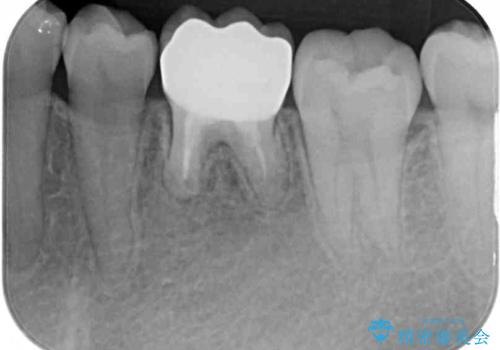

- 前歯のデコボコが気になるとのことで来院された患者様です。

目立たない装置と金属のワイヤーで矯正治療を行うこととしました。

奥の銀歯も気になっていたため、矯正治療後にセラミッククラウンにて補綴することとしました。